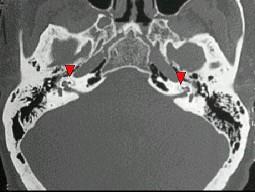

问题 男,43岁,进行性双侧耳鸣、听力下降5年,双侧混合聋,CT所见如图,最可能的诊断 ( )

选项 A、骨化性迷路炎 B、鼓室硬化症 C、嗜酸性肉芽肿 D、膜迷路畸形 E、耳硬化症

答案 E